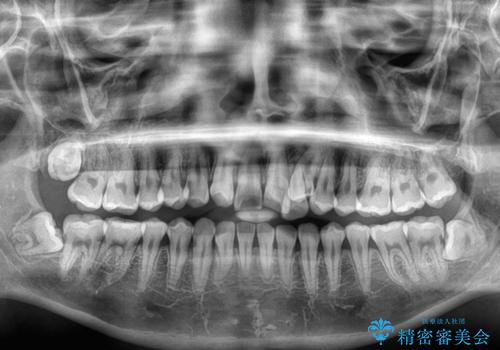

- 左上の前歯のがたつきを主訴に来院された患者様です。

上顎歯列が下顎の歯列に対して狭小であり、一部下顎の奥歯が上顎よりも外側に位置している状態でした。

上顎の歯列を拡大しスペースを設け、さらに左上の小臼歯を一本抜歯し左上の八重歯を歯列内に入れ整えていくことにしました。